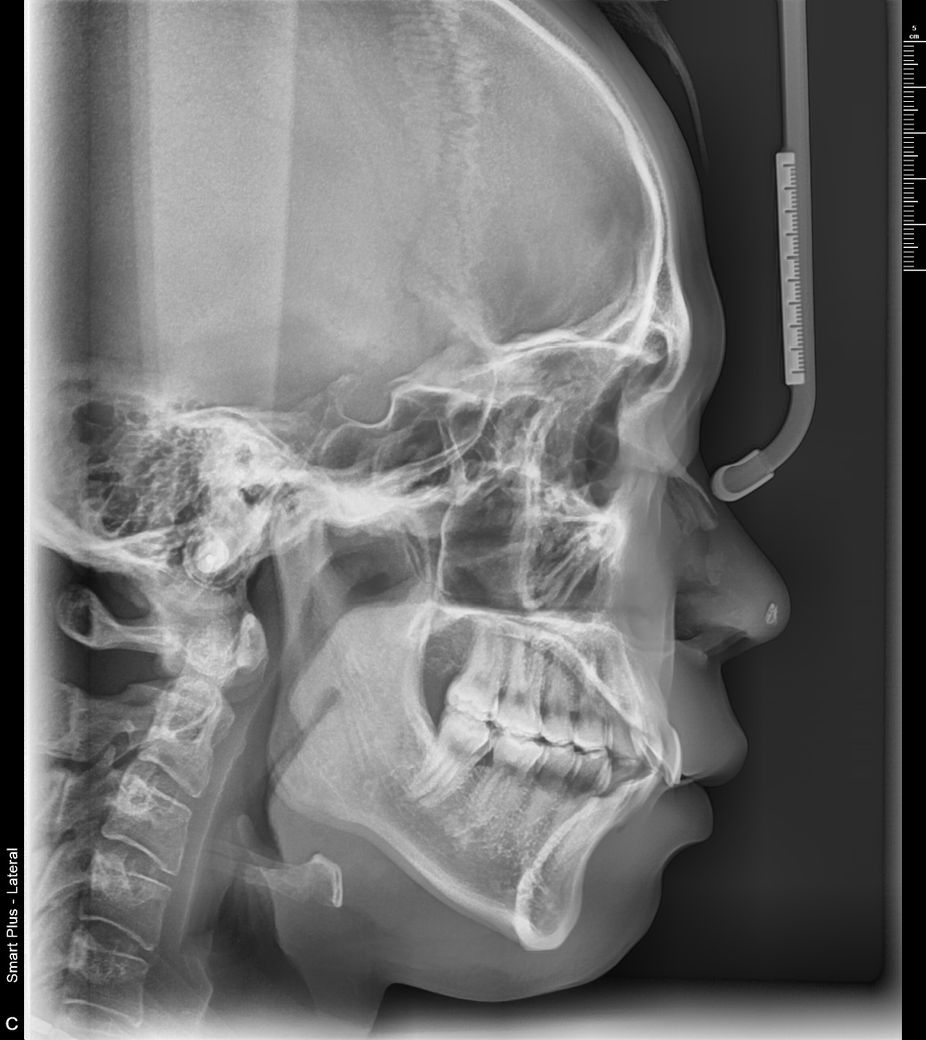

치아교정 잇몸돌출인가요?? 잇몸돌출교정을 해야될까요?

옆에서보면 입이 원숭이처럼 튀어 나와보이고 치아도 살짝 튀어나와있어 돌출입처럼 보입니다. 무턱증상도 약간 있고요. 제생각엔 잇몸 돌출때문에 더더욱 그런거같은데 잇몸 돌출이 되있는게 맞을까요??

x-ray 사진으로 보아 골격상으로는 전방돌출이 확인 안됩니다. 얼굴 외모로 보아 입술이 나와 보이거나, 웃을 때 윗입술이 위로 많이 올라가 잇몸이 많이 노출되는 경우도 있습니다.

교정분석을 해봐야 정확히 알겟지만, 골격적으로 문제가 잇을 가능성이 잇어 보입니다. 일단 교정 진단을 받아보세요.

위 사진상 봤을때 양악전돌 양상은 심하지 않으나 연조직 문제로 무턱, 돌출형 얼굴이 형성된 것 같습니다. 교정과나 구강악안면외과 치과에 가셔서 보다 자세한 상담을 받아보시기 바랍니다. 무턱교정의 경우 일반교정이 아니라 수술이 필요할 수도 있습니다.